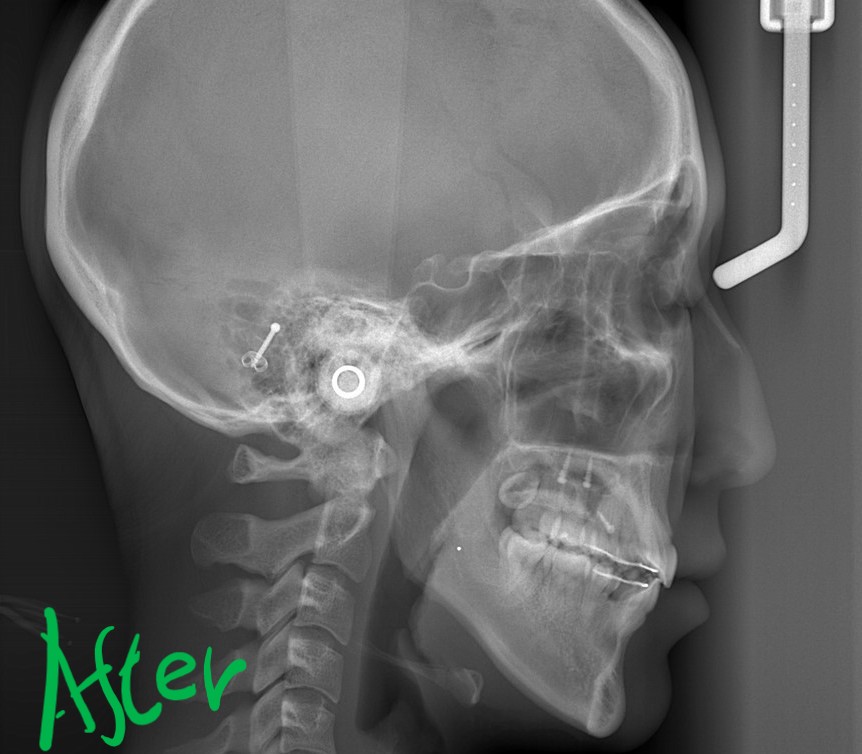

矯正後の状態をレントゲン写真で確認すると、

最後に、矯正治療前後の「レントゲン写真」と「口元の写真」の比較をお見せしましょう。

この患者さんにおいては、通常の抜歯で得られたスペース分を引っ込めた後、奥の智歯を抜歯してアンカースクリューも併用しながら更に奥へ引っ込める!という治療プランを実行しました。

それでは、その間の変化をレントゲン写真で見てみましょう。

右側が智歯を抜歯してアンカースクリューを併用しながら歯列全体を引っ込めた後の状態、

歯列の途中の奥歯を抜歯するほどには変化させられませんが、智歯という普通は抜歯だけで済ませる歯を利用することで、このように「もう一声!」口元の変化を起こすことも可能です。